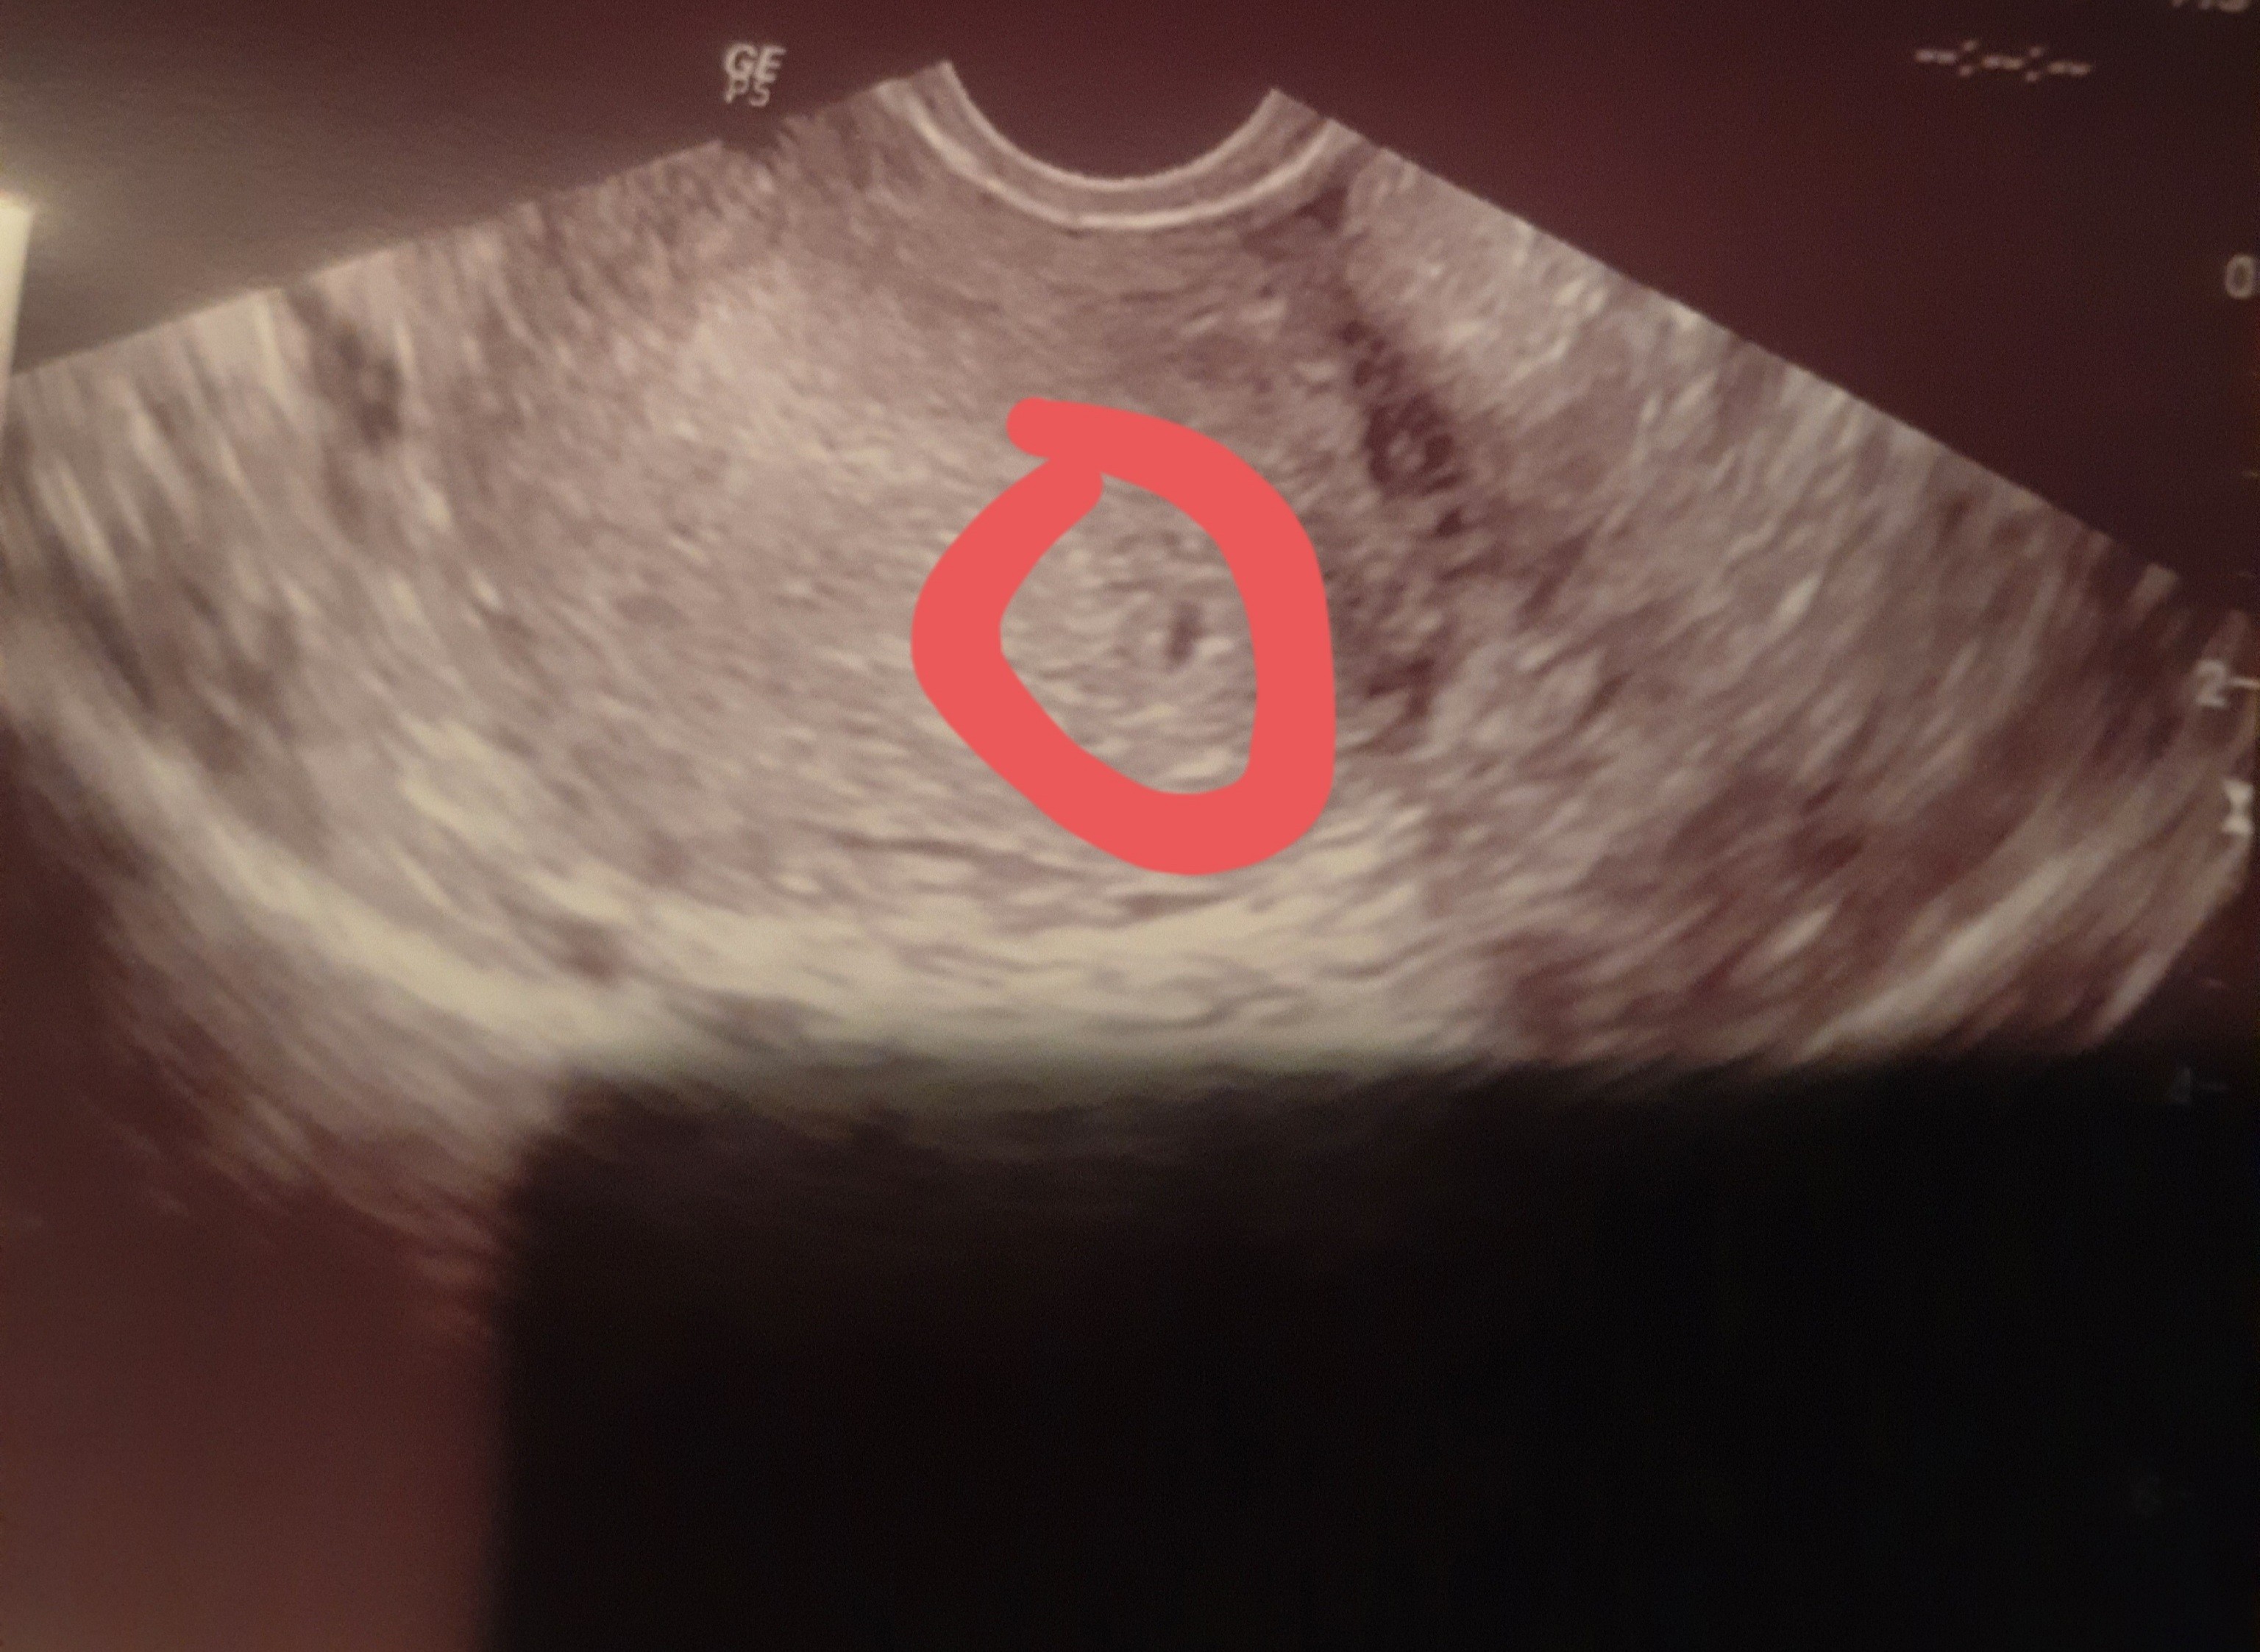

Niestety na wizycie pęcherzyk bardzo malutki. Z jednej perspektywy 0,29 cm, a z innej 0,19 cm). Pani Doktor powiedziała, że jest za mały na swój wiek, ale że może się rozwinąć. Mam przyjść za tydzień, 3.01.

Może jednak za bardzo się pospieszyłam i faktycznie jeszcze urośnie. To moja pierwsza ciąża. Miała któraś z Was już tak ?

Wydaje mi się ze jest za wcześnie a ciąża z usg może być młodsza 🙂

Ja dzisiaj 4+3, bylam u lekarza że względu względu wymioty i źle się czuję to tylko tyle zobaczyłam, następna wizyta 17.01